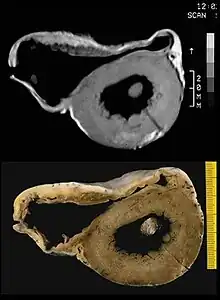

MRI

Fatty infiltration of the RV free wall can be visible on cardiac MRI. Fat has increased intensity in T1-weighted images. However, it may be difficult to differentiate intramyocardial fat and the epicardial fat that is commonly seen adjacent to the normal heart. Also, the sub-tricuspid region may be difficult to distinguish from the atrioventricular sulcus, which is rich in fat.

Cardiac MRI can visualize the extreme thinning and akinesis of the RV free wall. However, the normal RV free wall may be about 3 mm thick, making the test less sensitive.